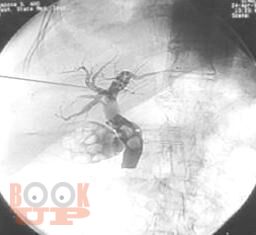

Методы диагностики механической желтухи

Методы диагностики механической желтухи : Учебно-методическое пособие / М. А. Агеев, Д. А. Славин, А. Н. Чугунов, Л. Е. Славин. - Казань : КГМА, 2018. - 48 c. - Текст : электронный // ЭБС "Букап" : [сайт]. - URL : https://www.books-up.ru/ru/book/metody-diagnostiki-mehanicheskoj-zheltuhi-16058875/ (дата обращения: 30.04.2026). - Режим доступа : по подписке.

Неотложная хирургия - одно из наиболее актуальных, сложных и ответственных направлений хирургии. Пациенты пожилого и старческого возраста с механической желтухой различной этиологии толстой кишки составляют значительный контингент, госпитализируемый в хирургические стационары по экстренным показаниям. Издание реализовано с учетом опыта сотрудников кафедры и современных представлений о патогенезе, методах эндоскопической диагностики, клинических проявлениях и основных принципах лечения больных синдромом механической желтухи, обусловленной осложнениями патологии гепатопанкреатодуоденальной зоны и желудочно-кишечного тракта. Успех в лечении таких пациентов во многом зависит от своевременности и точности постановки диагноза.